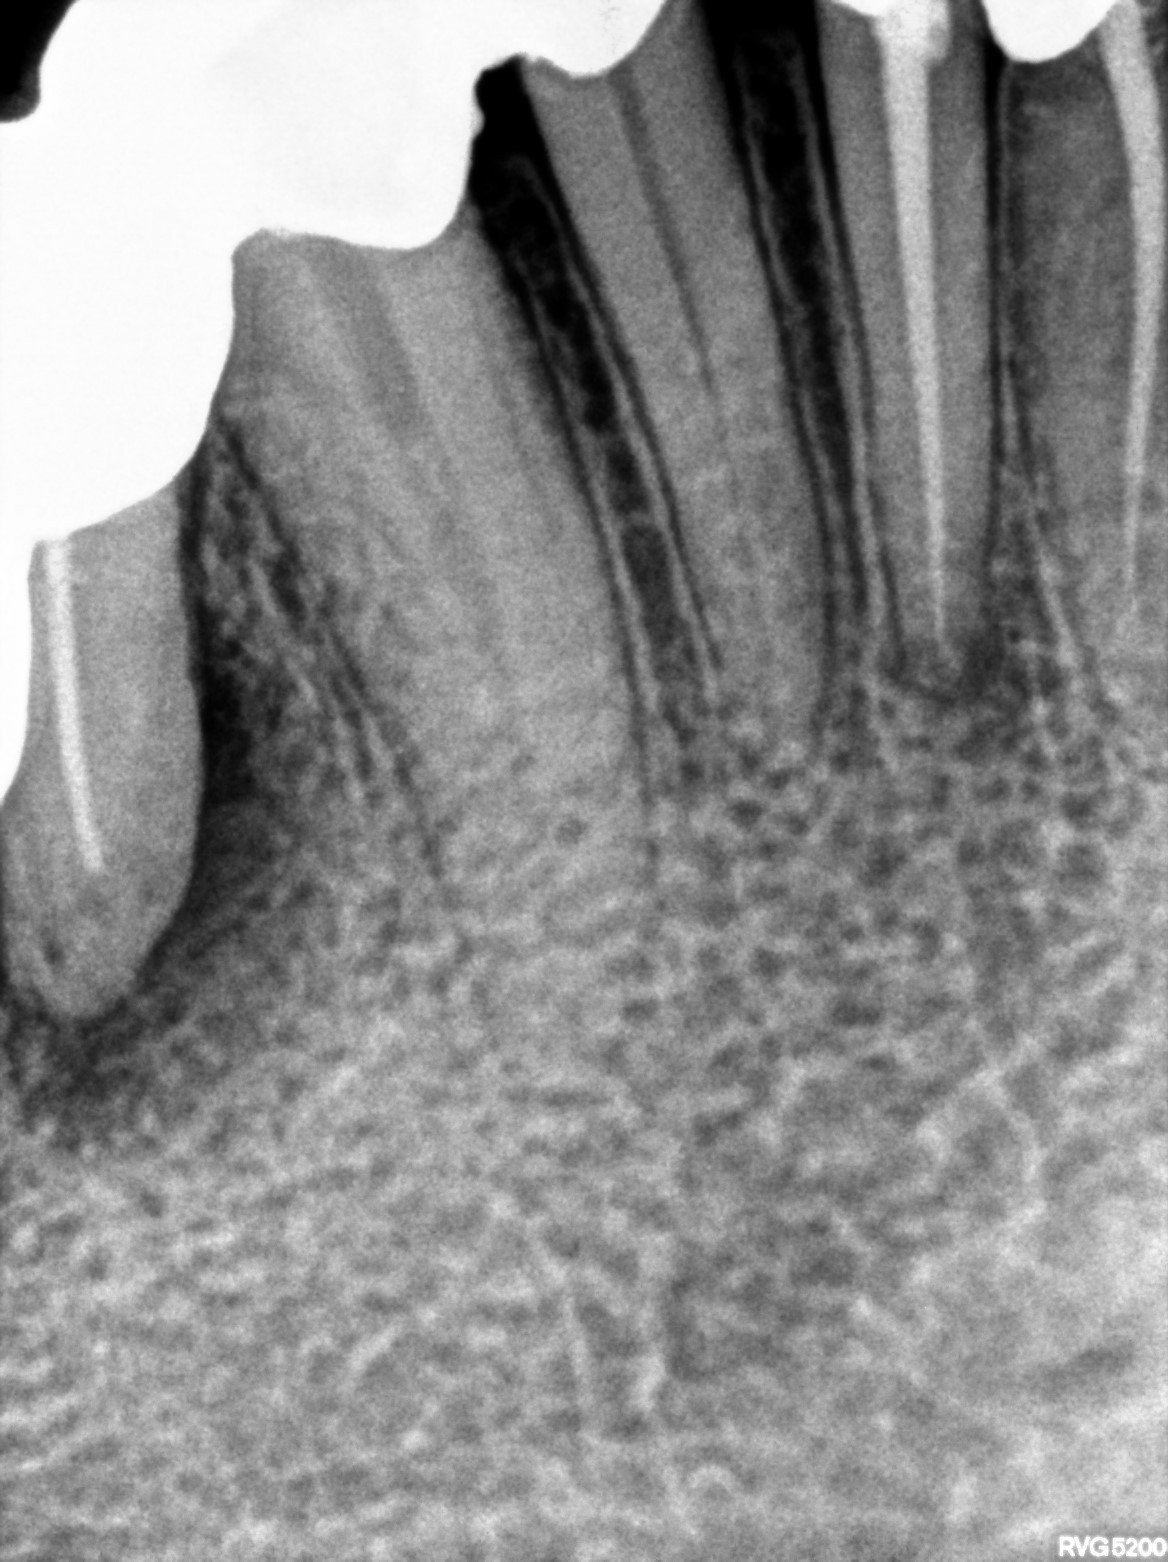

Dental Radiographs FHIR: DocumentReference · LOINC 24641-7

xray_1765005927_0.jpg

24641-7

xray_1763362538_4.jpg

xray_1764234367_1.jpg

xray_1763362538_0.jpg

xray_1763362542_4.jpg

xray_1764234367_0.jpg

xray_1763362538_5.jpg

xray_1763362542_5.jpg

xray_1764234367_2.jpg

xray_1764402791_0.jpg

xray_1773905527_1.jpg

xray_1763362541_0.jpg

xray_1763362541_1.jpg

xray_1763362542_2.jpg

xray_1763362538_2.jpg

xray_1763362538_1.jpg

xray_1763362538_3.jpg

xray_1763362542_3.jpg

xray_1773905527_0.jpg